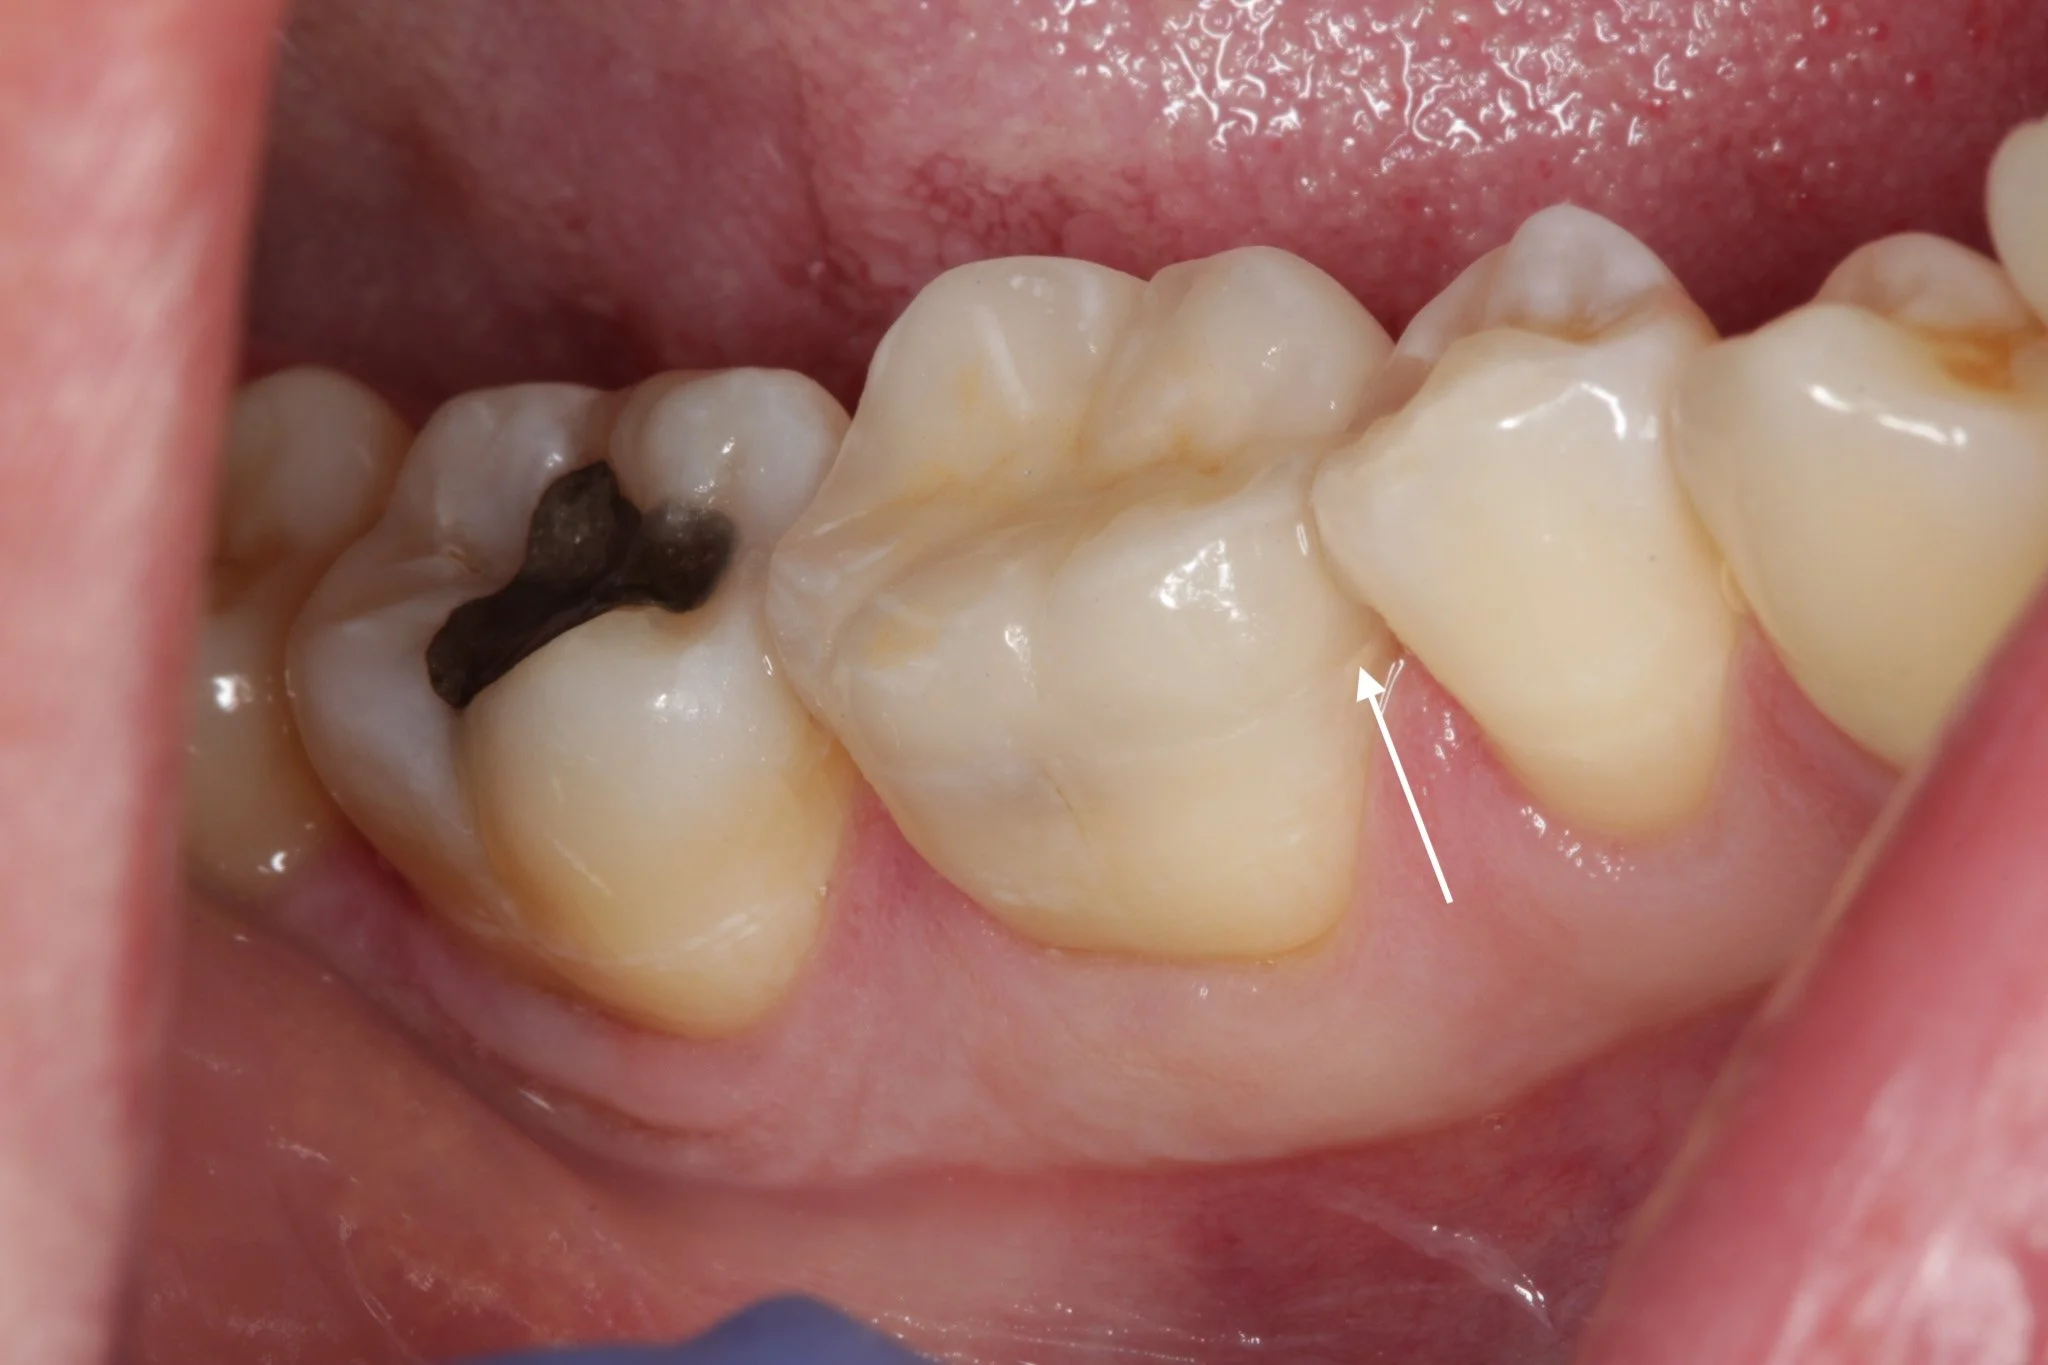

Decay most commonly starts at the edges of the onlay, known as the margins. If plaque builds up here, bacteria can creep underneath the restoration and cause decay that is not always visible.

The margin of an onlay where the onlay meets the natural tooth underneath